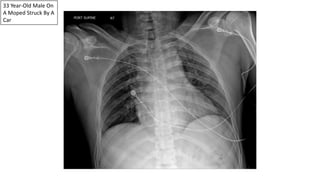

33 Year-Old Male On

A Moped Struck By A

Car

Wide

Mediastinum

Traumatic Aortic Disruption